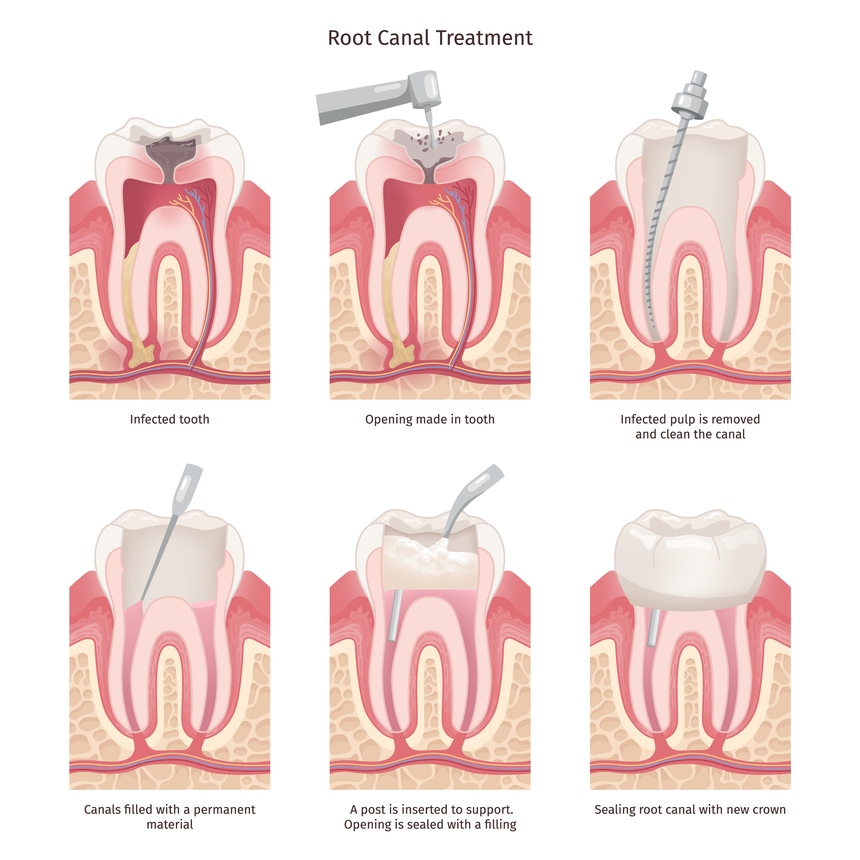

Painless Root Canal Treatment in Mahatma Nagar Nashik

Looking for a reliable and pain-free solution for your root canal treatment in Mahatma Nagar Nashik At Care 32 Dental an...

Painless Root Canal Treatment in Gangapur Road Nashik

If you are experiencing severe tooth pain or sensitivity, a root canal treatment might be the best solution to save your...